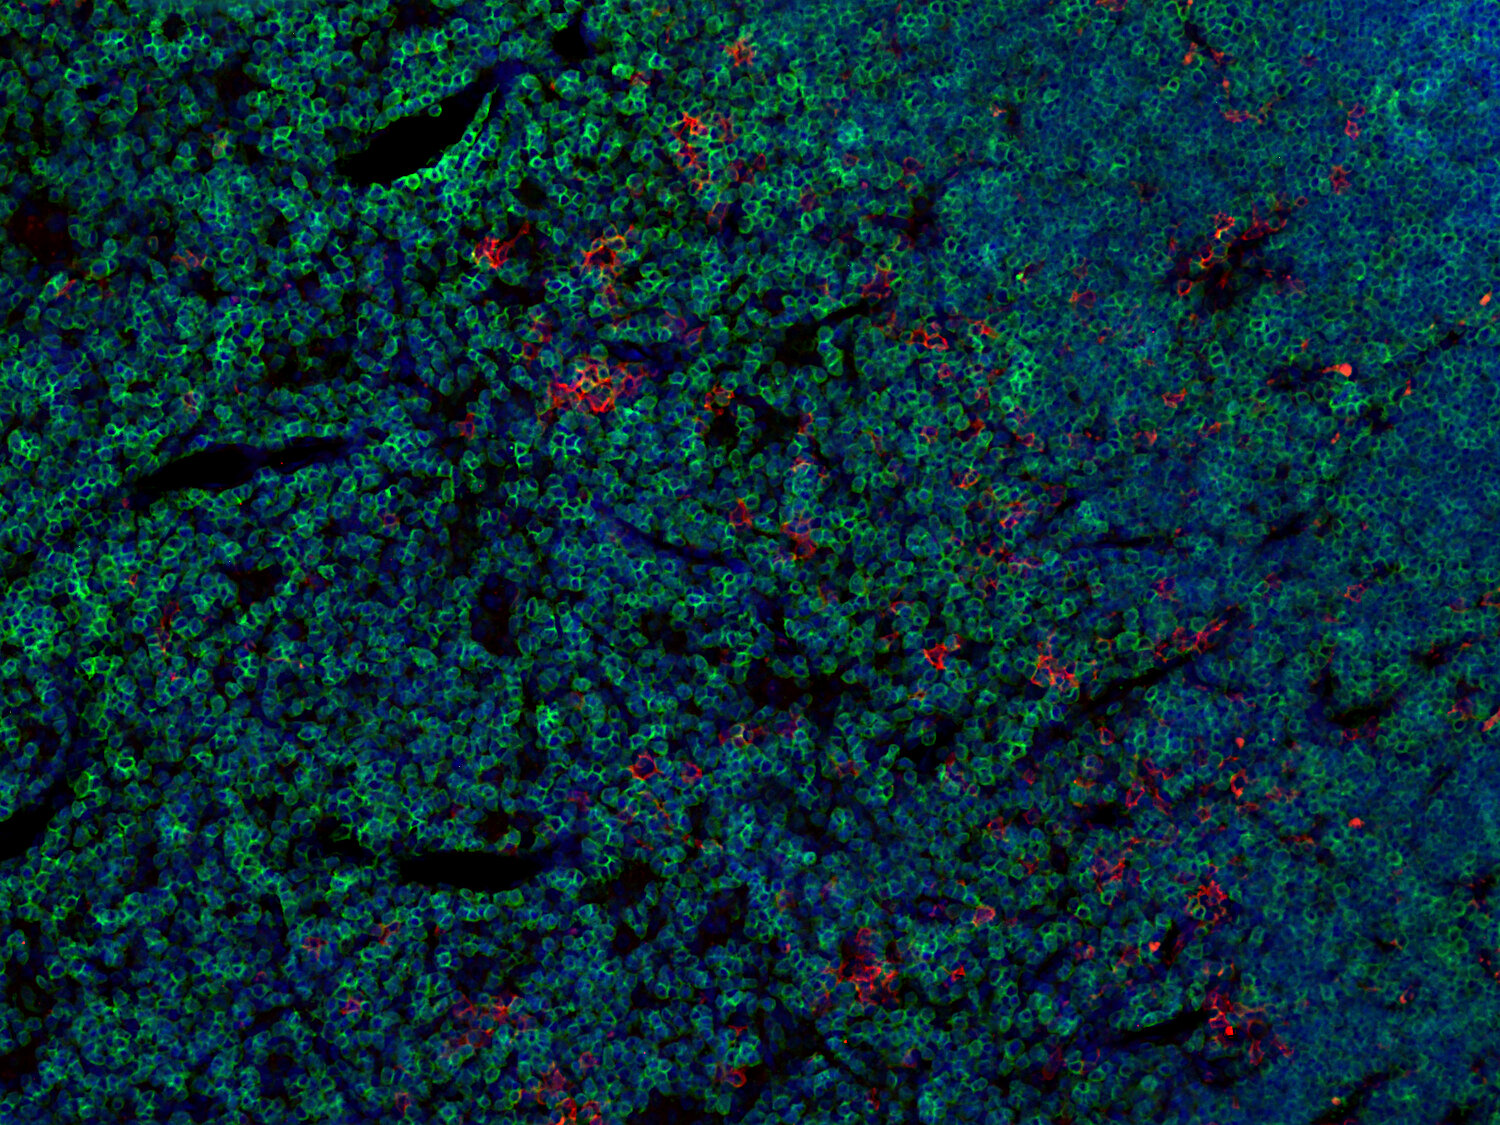

Fluorescent double staining for CD19 (red) and CD3e (green) visualizes B-cell and T-cell populations in the mouse spleen